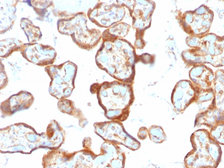

Images